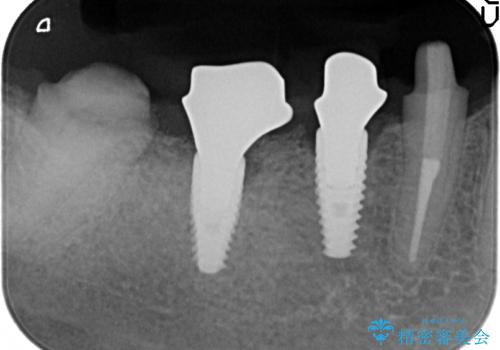

- 右下でものを咬むと痛むので診て欲しいといらっしゃった方の症例です。

右下6番目の歯を診査したところ歯根が破折していたため、保存不可能であることを説明し抜歯しました。

その後右下5、6番目にはインプラントを埋入し、右下3、4、5、6、7番の歯の補綴をオールセラミッククラウンによって行いました。

- オールセラミッククラウン…¥100,000×5、仮歯…¥10,000×5、インプラント(ストローマン)…¥200,000×2、カスタムアバット…¥100,000×2、骨増生…¥50,000費用は治療当時の料金となります